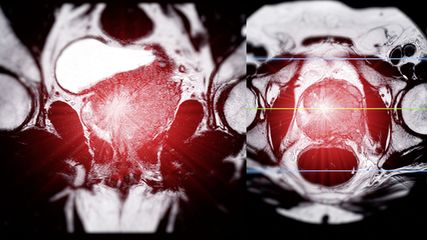

M. Becker: Deshalb gehört jede Visusstörung bei jedem Patienten abgeklärt, inklusive Bildgebung und ophthalmologischer Beurteilung. Bei hinreichendem Verdacht auf eine kraniale Riesenzellarteriitis muss umgehend behandelt werden. Insbesondere Patienten mit Claudicatio masticatoris oder mit peripherer Vaskulopathie – etwa aufgrund einer Arteriosklerose – sind gefährdet.5 Vorübergehende Erblindung ist ein Warnsignal, und auch wenn schon ein Auge erblindet ist, muss eine konsequente Therapie erfolgen, um das zweite Auge zu schützen. Man kann es nicht oft genug wiederholen: Die frühe Diagnose und vor allem rechtzeitige Therapie bei Verdacht sind das A und O. Mithilfe umfassenderer genetischer und zellulärer Analysen können wir in Zukunft hoffentlich aber auch Patienten mit bestehender Diagnose besser einteilen und mit neuen Medikamenten gezielter therapieren.